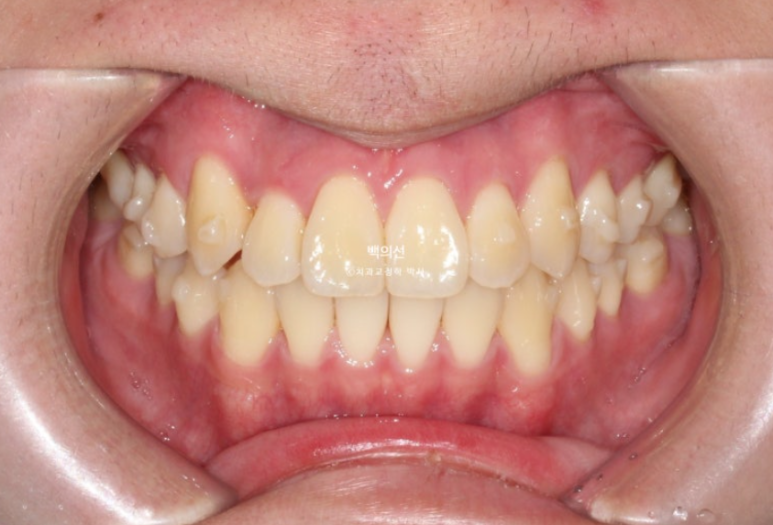

12월까지 장치 하나당 열흘에서 2주씩 착용했고 12월 겨울방학이 되어 내원한 모습입니다.

24.12

덧니와 반대교합은 해소가 되었습니다.

교합은 좋고 양쪽 다 1급 교합관계를 보입니다.

배열도 완벽 합니다.